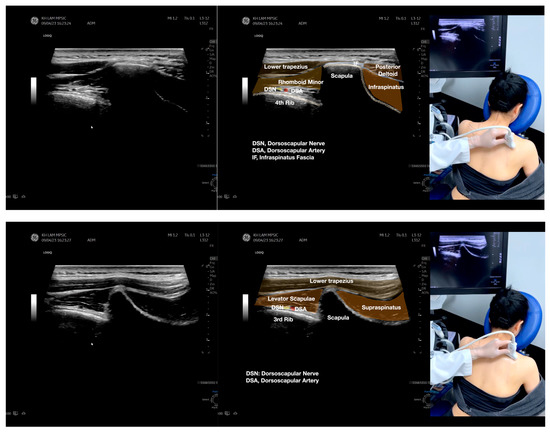

Figure 4.

Sonoanatomy of the medial edge of the scapula, its related muscles, and the infraspinatus fascia. The step-by-step scanning techniques of these structures illustrated in this figure have been shown in Video S8. Available online: https://www.dropbox.com/s/iaej3rxhl83kqt4/Figure%204.docx?dl=0 (accessed on 1 January 2023).